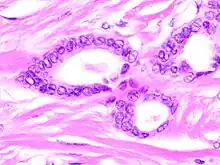

Tubular carcinoma is a subtype of invasive ductal carcinoma of the breast.[2][3] More rarely, tubular carcinomas may arise in the pancreas[4] or kidney.[5] Most tubular carcinomas begin in the milk duct of the breast and spread to healthy tissue around it.[6][7]

Although tubular carcinoma has been considered a special-type tumor,[lower-alpha 1] recent trend has been to classify it as a low-grade, invasive NOS carcinoma because there is a continuous spectrum from pure tubular carcinomas to mixed NOS[lower-alpha 2] carcinomas with tubular features, depending on the percentage of the lesion that displays tubular features.[10]: 647

Tubular carcinomas are generally around 1 cm. or smaller, and are made up of tubules. They are usually low-grade.[2] Elastosis has been noted as common but is not present in all cases.[11]

A highly differentiated invasive carcinoma that forms well-defined tubules (containing epithelium, but no myoepithelium) and that have abundant desmoplastic fibrous stromal reaction between the tubules.